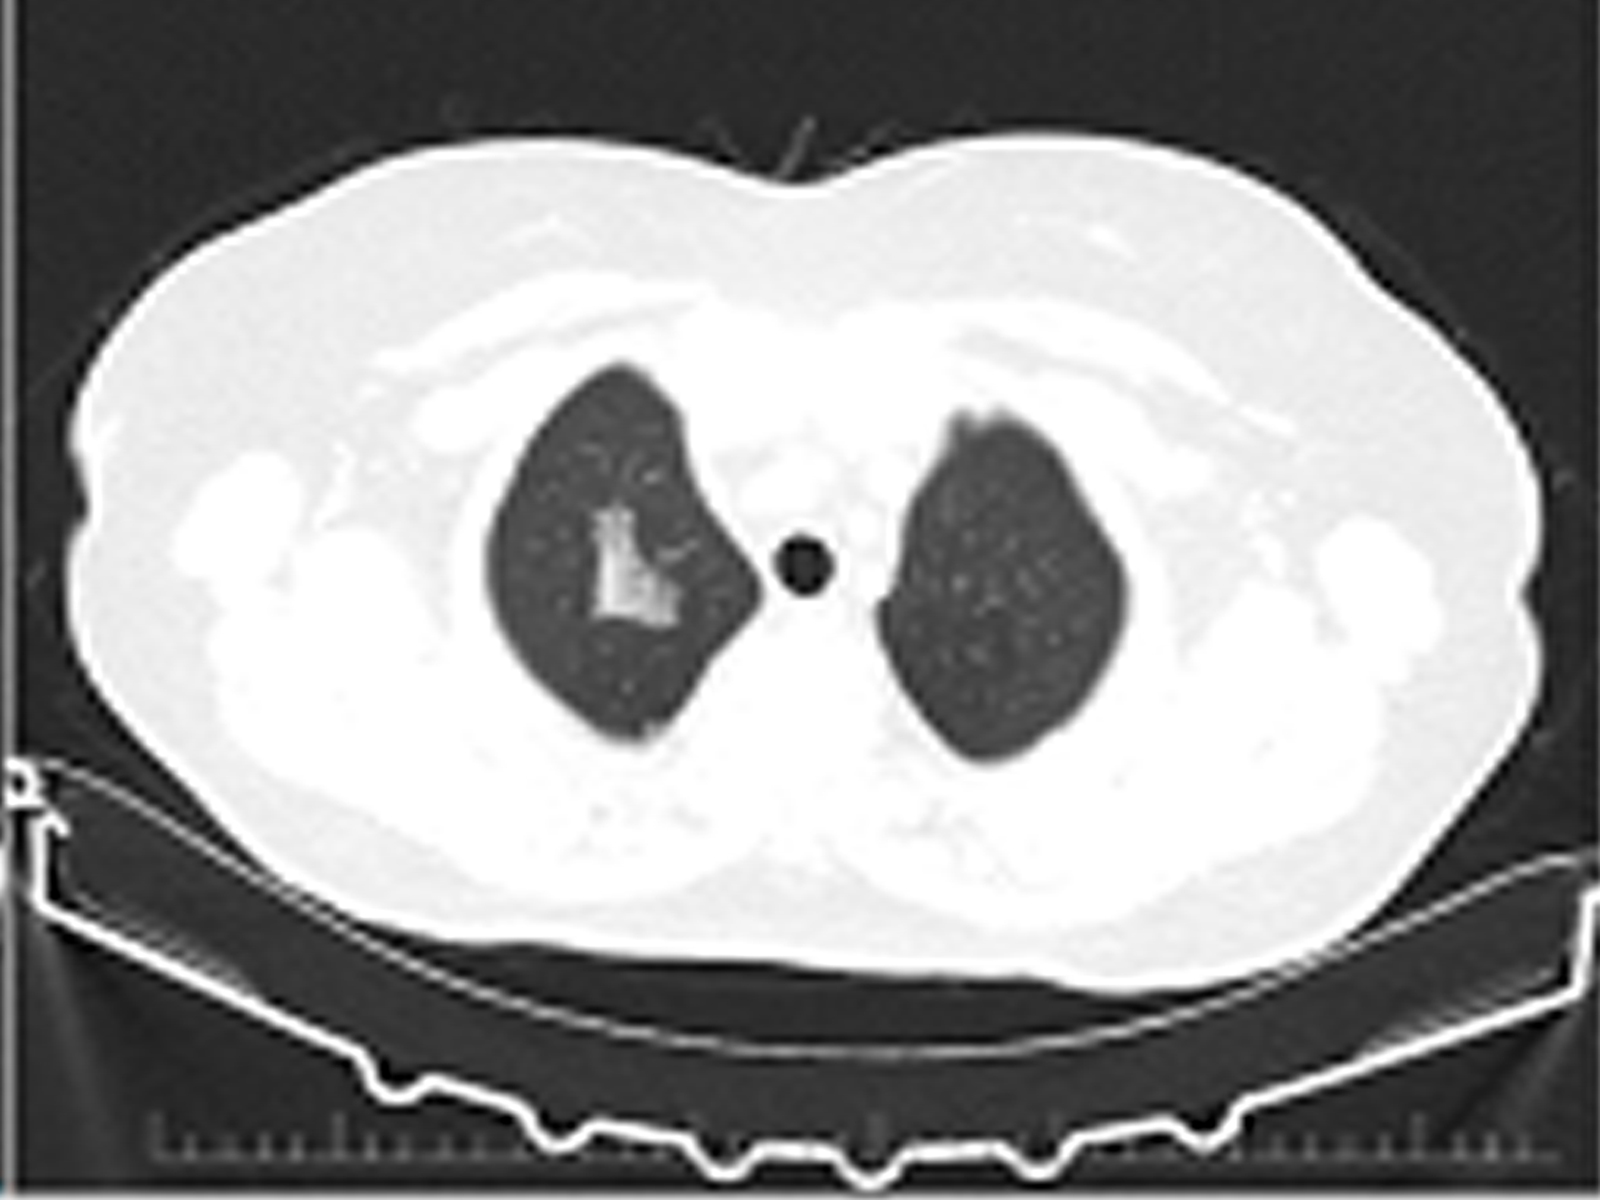

EVALI Case Report: A New Form of Self-Destruction

Fidan Layijova, Alper Gündüz, Nilsu Buket Ercan, Bilge Kaan Er, Elif Kupeli doi: 10.5505/respircase.2026.78736 Pages 1 - 4 |